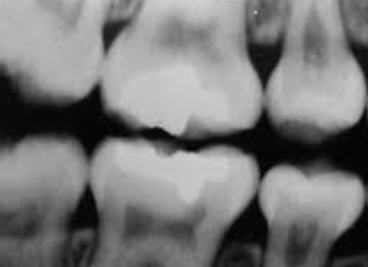

single enlarged/ double/ jointed tooth in which the tooth count is normal (NO MISSING TEETH); one tooth bud tried to divide

gemination

defined as a single/ enlarged/ double/ joined tooth in which the tooth count reveals a MISSING tooth; two buds tried to join

fusion